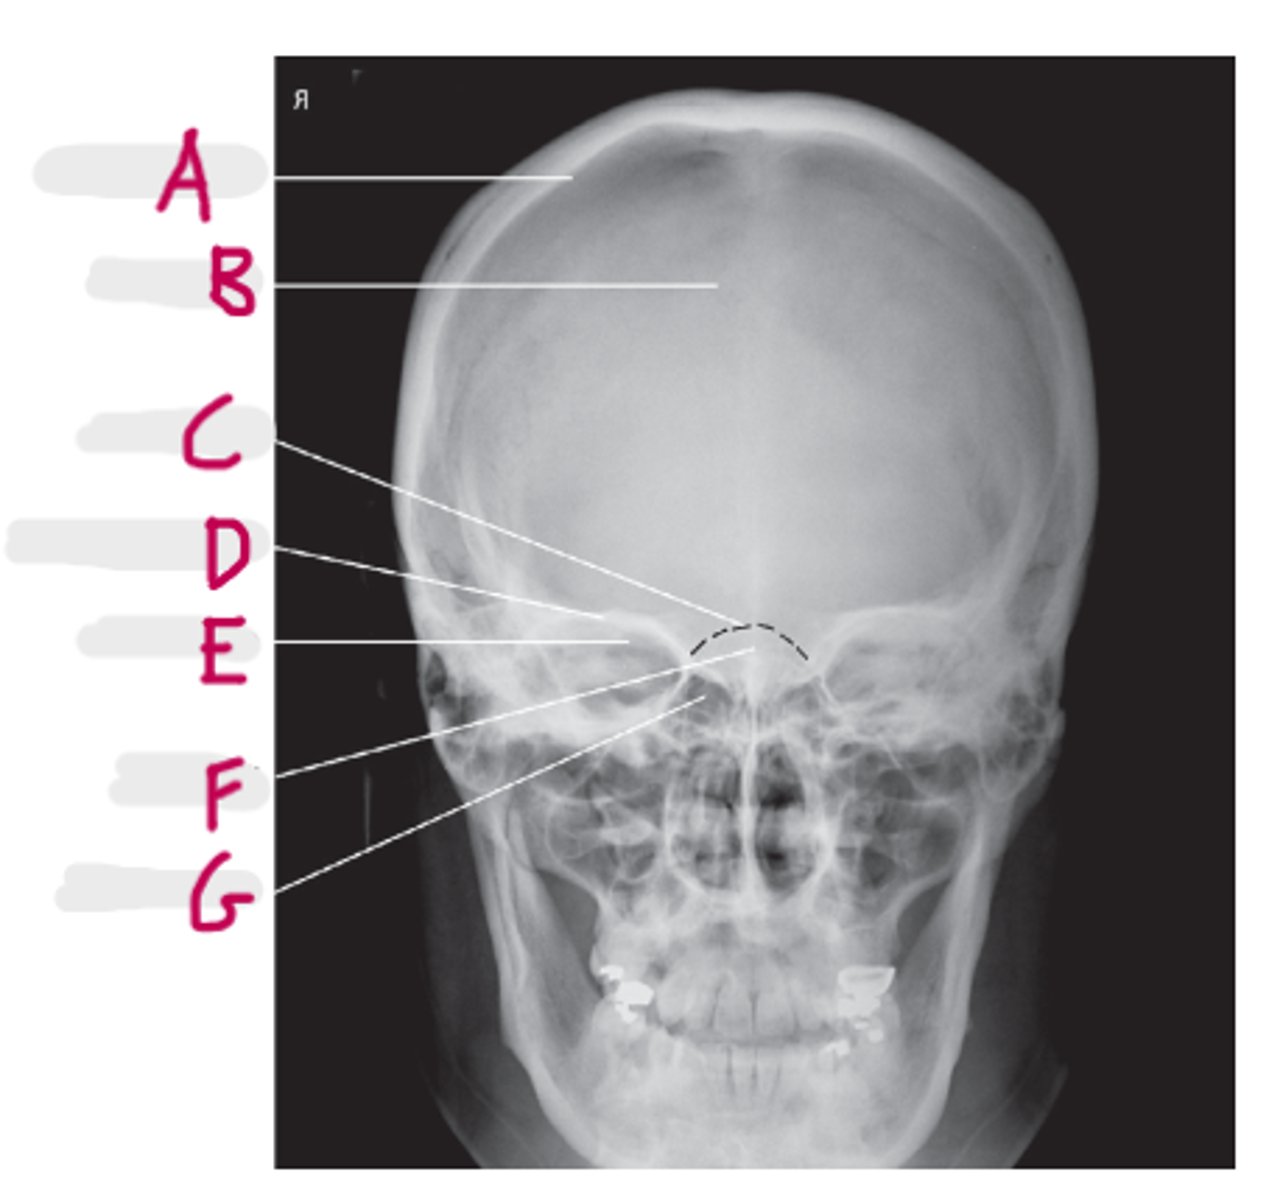

Coronal Suture

A

Orbital roof

B

Sella turcica

C

Sphenoid sinus

D

Petrous portion of temporal bone

E

Temporomandibular joint

F (jt)

EAM

G

Mandibular rami

H